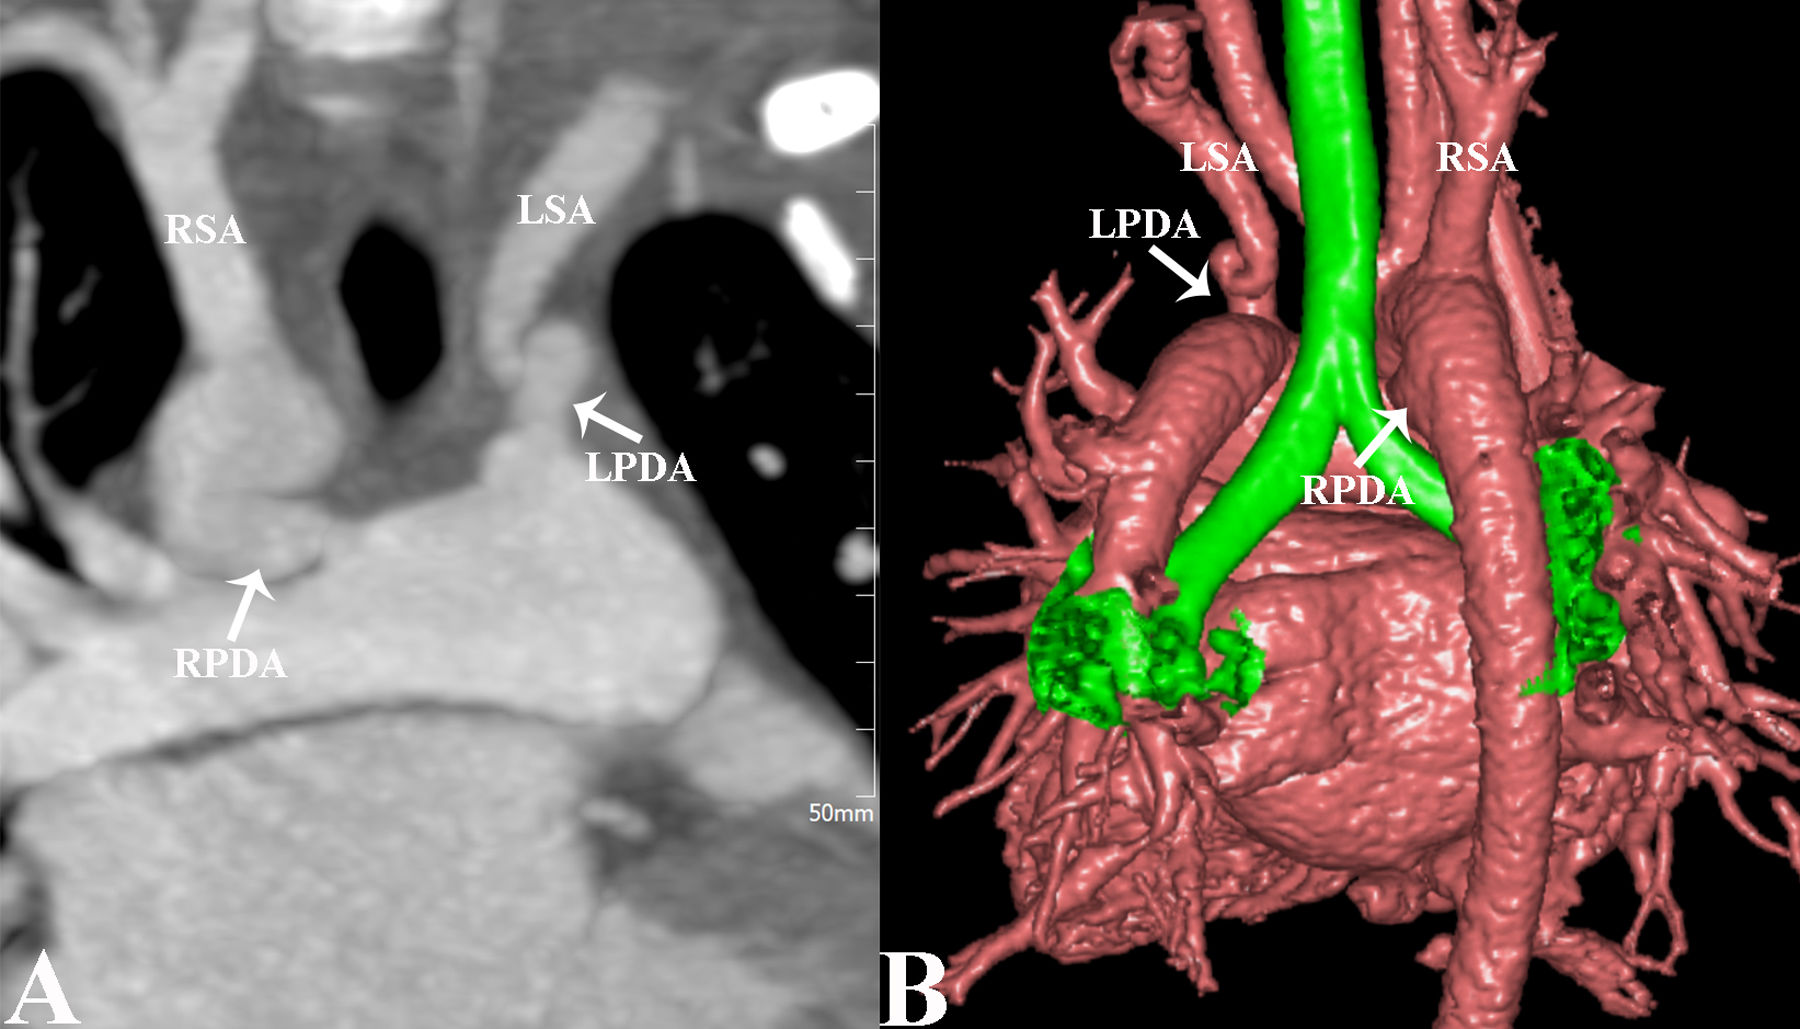

A two-year-old girl was admitted to the hospital following the incidental discovery of a heart murmur three days previously. A grade 3/6 continuous murmur was audible near the left sternal border at the second intercostal space. Chest X-ray suggested increased bilateral pulmonary blood flow and cardiomegaly. Transthoracic echocardiography revealed the right aortic arch (RAA), patent ductus arteriosus (PDA) and the left subclavian artery (LSA) originating from the pulmonary artery. Computed tomography angiography (CTA) images showed a bilateral ductous arteriosus with concomitant combinations of RAA and isolated LSA. Right-sided PDA connected from the descending aorta to the right pulmonary artery and left-sided PDA connected the LSA to the left pulmonary artery with meandering and narrowing (Figure 1A and B). The patient underwent bilateral PDA ligation and LSA reconstruction under cardiopulmonary bypass. Postoperative recovery was uneventful, and the patient was discharged after seven days.

(A) Maximal intensity projection (MIP) of computed tomography angiography (CTA) images with a coronal image shows bilateral patent ductus arteriosus with an isolated left subclavian artery originating from the left pulmonary artery. (B) Three-dimensional volume rendering (3D VR) of CTA image shows a bilateral arteriosus with concomitant combinations of RAA and isolated LSA. Right-sided PDA connected from the descending aorta to the right pulmonary artery and left-sided PDA connected the LSA to the left pulmonary artery with meandering and narrowing. RIA, right innominate artery; LSA, left subclavian artery; LPDA, left patent ductus arteriosus; RPDA, right-sided patent ductus arteriosus.